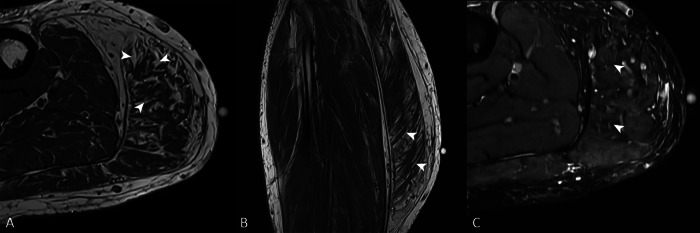

Teaching point: Denervation pseudohypertrophy of the medial gastrocnemius muscle is an uncommon cause of calf swelling that may be secondary to chronic radiculopathy.